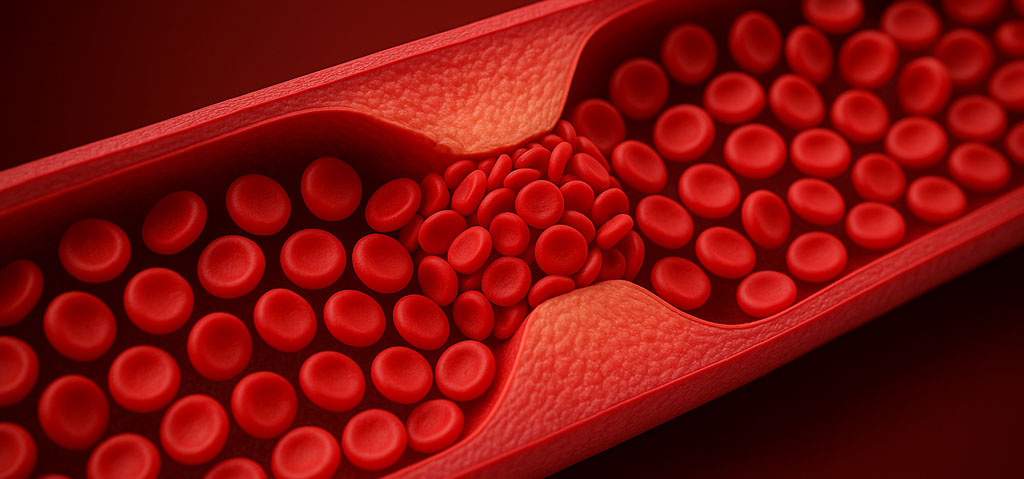

Långa resor med stillasittande på flyg, tåg och i bil ökar risken för djup ventrombos i de stora venerna i benen, vilka sedan kan lossna och färdas till lungorna som en lungemboli (venös tromboembolism – VTE), ett potentiellt livshotande tillstånd. VTE kan förebyggas genom att röra på benen under resan och eventuellt bära stödstrumpor.

Vid längre flygresor ökar risken för blodproppar i benen och lungorna. Detta beror främst på att man sitter stilla länge med begränsad möjlighet att röra på sig. Blodet i de stora venerna kan då lätt stockas i benen i stället för att flöda tillbaka till hjärtat. När benen hela tiden trycker mot sätet blir blodflödet tillbaka till hjärtat ännu sämre, och trycket kan dessutom skapa en irritation i blodkärlens väggar.

Detta kan ibland leda till att en djup ventrombos (DVT) bildas i en av de stora venerna i något av benen. En liten del av en sådan propp kan sedan lossna och och orsaka en lungemboli. En plötslig stor lungemboli kan vara ett livshotande tillstånd.